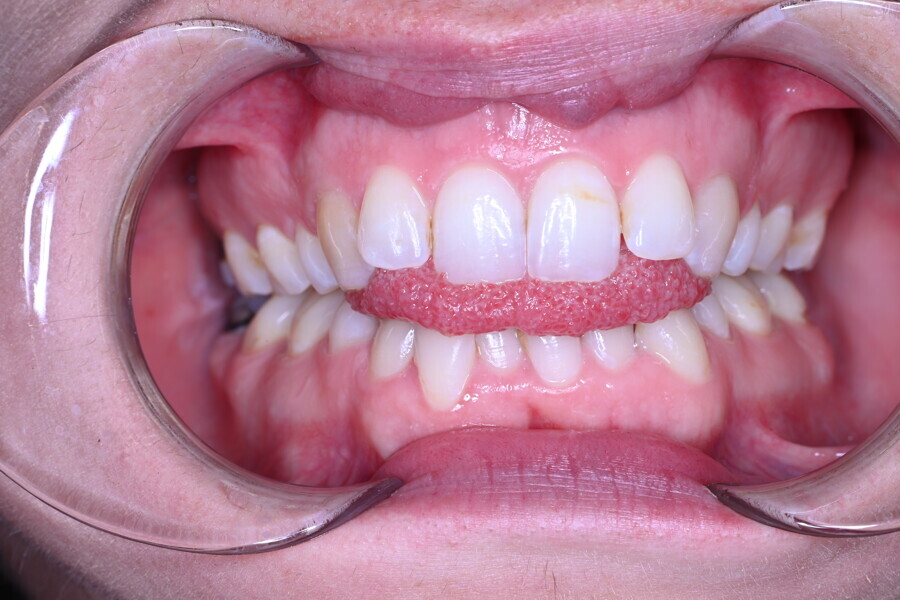

The 58-year-old patient wished to improve his oral aesthetics and function, complaining of mobility of the posterior teeth and wear of the anterior teeth. After data collection, a very complex situation was identified (Figs. 11–13):

1. severe periodontitis with poor prognosis of some teeth;

2. anterior crossbite;

3. severe wear mainly of the anterior teeth and compensatory eruption;38

4. atypical swallowing and lower posture of the tongue at rest;

5. masticatory dysfunction during the mastication test; and

6. no significant signs of temporomandibular disorder.

After the first phase of aligner treatment, we had achieved better inter-arch coherence, better maxillary arch expansion, and some space for improving the anterior tooth proportions restoratively (Fig. 19). We then temporarily restored the anterior teeth directly with composite, closing the spaces, improving the tooth proportions and further increasing the maxillary arch expansion (Fig. 20). We used restorative arch expansion to reduce the orthodontic destabilisation of the teeth to achieve the correct inter-arch coherence and retain the teeth in the cortical bone.38 A refinement aligner phase was undertaken to improve the final alignment of the gingival zenith and to improve the inter-arch coherence (Fig. 21). The periods of the first orthodontic phase and of the refinement were used to augment the mandibular and maxillary bone and to place the implants (Fig. 22). At the end of the orthodontic treatment, the case was finalised with ceramic veneers in the anterior area and temporary restorations on the implants in the posterior area (Figs. 23–26).